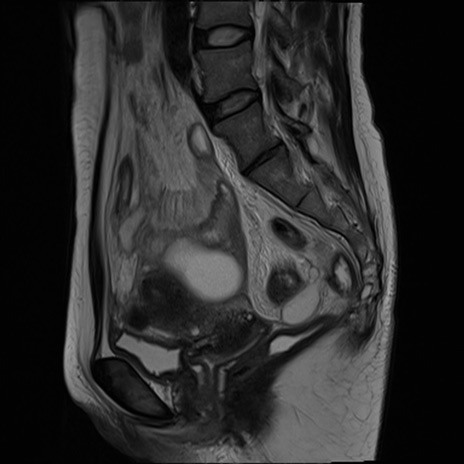

症例39 T2WI(矢状断像)

MRI(4日後)